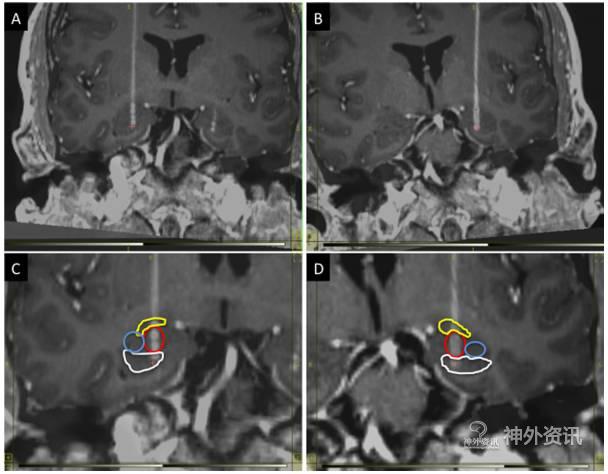

末次随访时的刺激参数为,右侧电极:电压1.4V,脉宽60μs,频率160Hz;左侧电极:电压0.7V,脉宽60μs,频率160Hz。术后5个月时曾将刺激电压提高到右侧2.0V、左侧1.1V后,CAPS评分改善率减低(图2)。术后CT与术前MRI的融合图像证实电极植入位点准确(图3)。

图3. 术后CT与术前MRI冠状面融合图像显示的电极轨道。A. 电极植入右侧BLn;B. 电极植入左侧BLn;C、D. 电极的4个触点分别位于不同的核团:黄色代表中央核(1个触点),红色代表BLn(2个触点),蓝色代表海马(1个触点)。